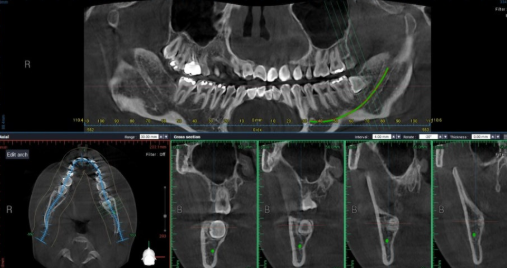

사랑니가 깊게 매복되었거나, 임플란트 수술이 계획된 환자에서 촬영하는

"치과용 CT" 입니다. 30 μSv 정도 방사선이 인체에 흡수됩니다.

파노라마 3장 촬영하는 수준입니다.